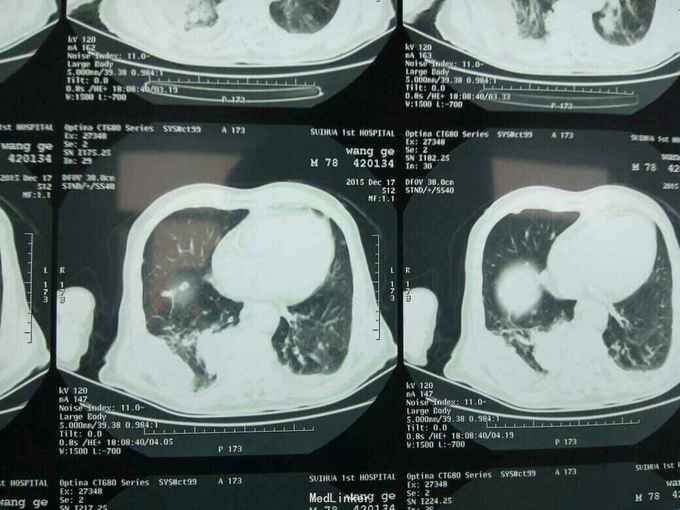

根据病史查体诊断:腰间盘突出症待确诊。应用消肿营养神经镇痛治疗。一天。查核磁共振示:腰椎多节段间盘突出伴椎管狭窄。第二腰椎骨破坏侵及椎板。部分突入椎管,脊髓受压。诊断:腰间盘突出伴椎管狭窄。第二腰椎转移癌,脊髓受压。经与家属沟通,查双肺CT:双肺下叶炎症。肺部纤维化。可见肿瘤阴影。肋骨及胸膜受累。胸椎部分骨破坏。最终诊断:双肺癌,胸椎,腰椎骨转移,脊髓受压。多节段腰椎间盘突出。病人至肿瘤科治疗。